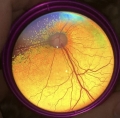

アジア獣医眼科設立専門医による眼科専門外来

数カ月に1回、眼科専門外来を実施しています

伊藤 良樹 先生(岡山理科大学准教授)

医学博士、アジア獣医眼科設立専門医

獣医眼科学、視覚電気生理学

アジア獣医眼科設立専門医の伊藤先生による眼科検査と診断を行います。

必要な検査を飼い主様と相談の上で実施いたします。

眼科検査例

- スリット検査

- 眼圧検査

- 眼底検査

- 眼科超音波検査

- 染色検査

- 散瞳検査

- 涙液量検査

- 隅角鏡検査